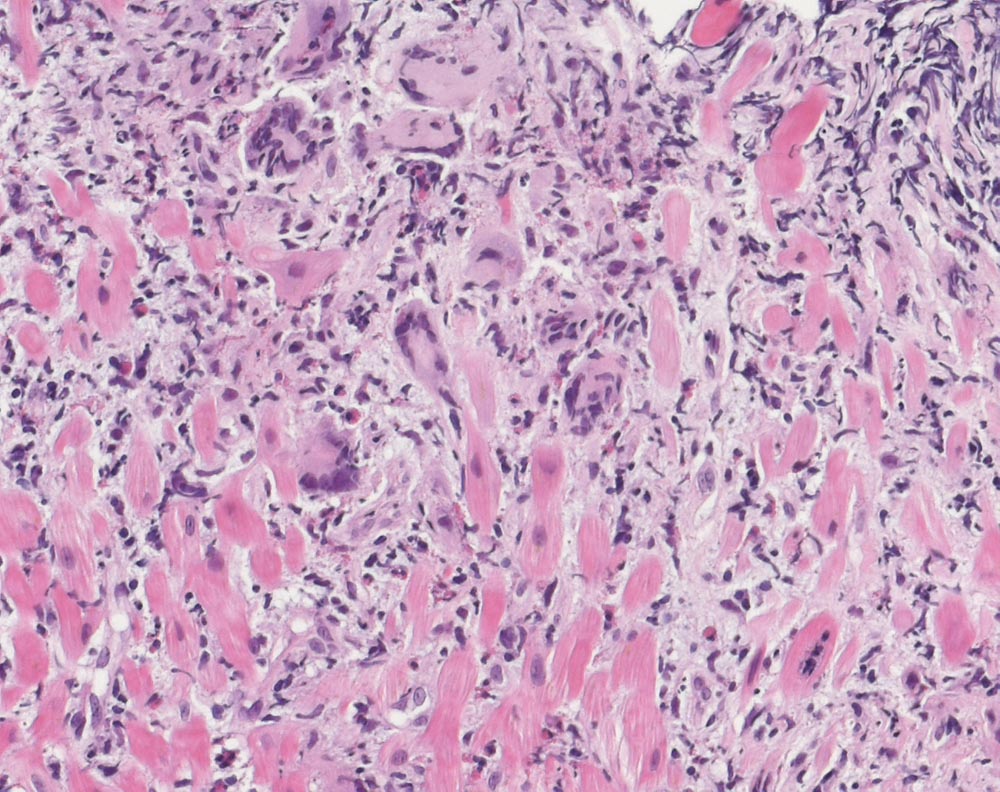

Floride Riesenzellmyokarditis

Innerhalb des Myokards findet man massenhaft Infiltrate von Lymphozyten, Histiozyten sowie zahlreichen eosinophilen Leukozyten. Dazwischen sind immer wieder einzelne Riesenzellen eingestreut, die teils myogenen Riesenzellen, teils Histiozyten entsprechen. Die Herzmuskulatur ist im Bereich der Infiltrate landkartenförmig zerstört. Die erhaltene Herzmuskulatur zeigt keine Auffälligkeiten.

Ausschluss einer Infektion mit kardiotropen Erregern in den durchgeführten in situ Hybridisierungen und den nested PCR-Untersuchungen, insbesondere kein Nachweis von EV, PV- B19, HHV-6, EBV, ADV oder HCMV. Massives myokardiales Entzündungsinfiltrat zu 70% aus T-Zellen, zu 20% aus B-Zellen und zu 10% aus Monozyten/Makrophagen bestehend. Massive Hochregulation von HLA-DR im Endothel. Lichtmikroskopisch auch eosinophile Leukozyten nachgewiesen. Die lichtmikroskopisch beschriebenen Riesenzellen sind zum Teil schwach positiv für CD68 (d.h. zum Teil histiozytären Ursprungs).

Repetive Reanimationen und progrediente Verschlechterung der Ejektionsfraktion. Myokarditis unklarer Ätiologie